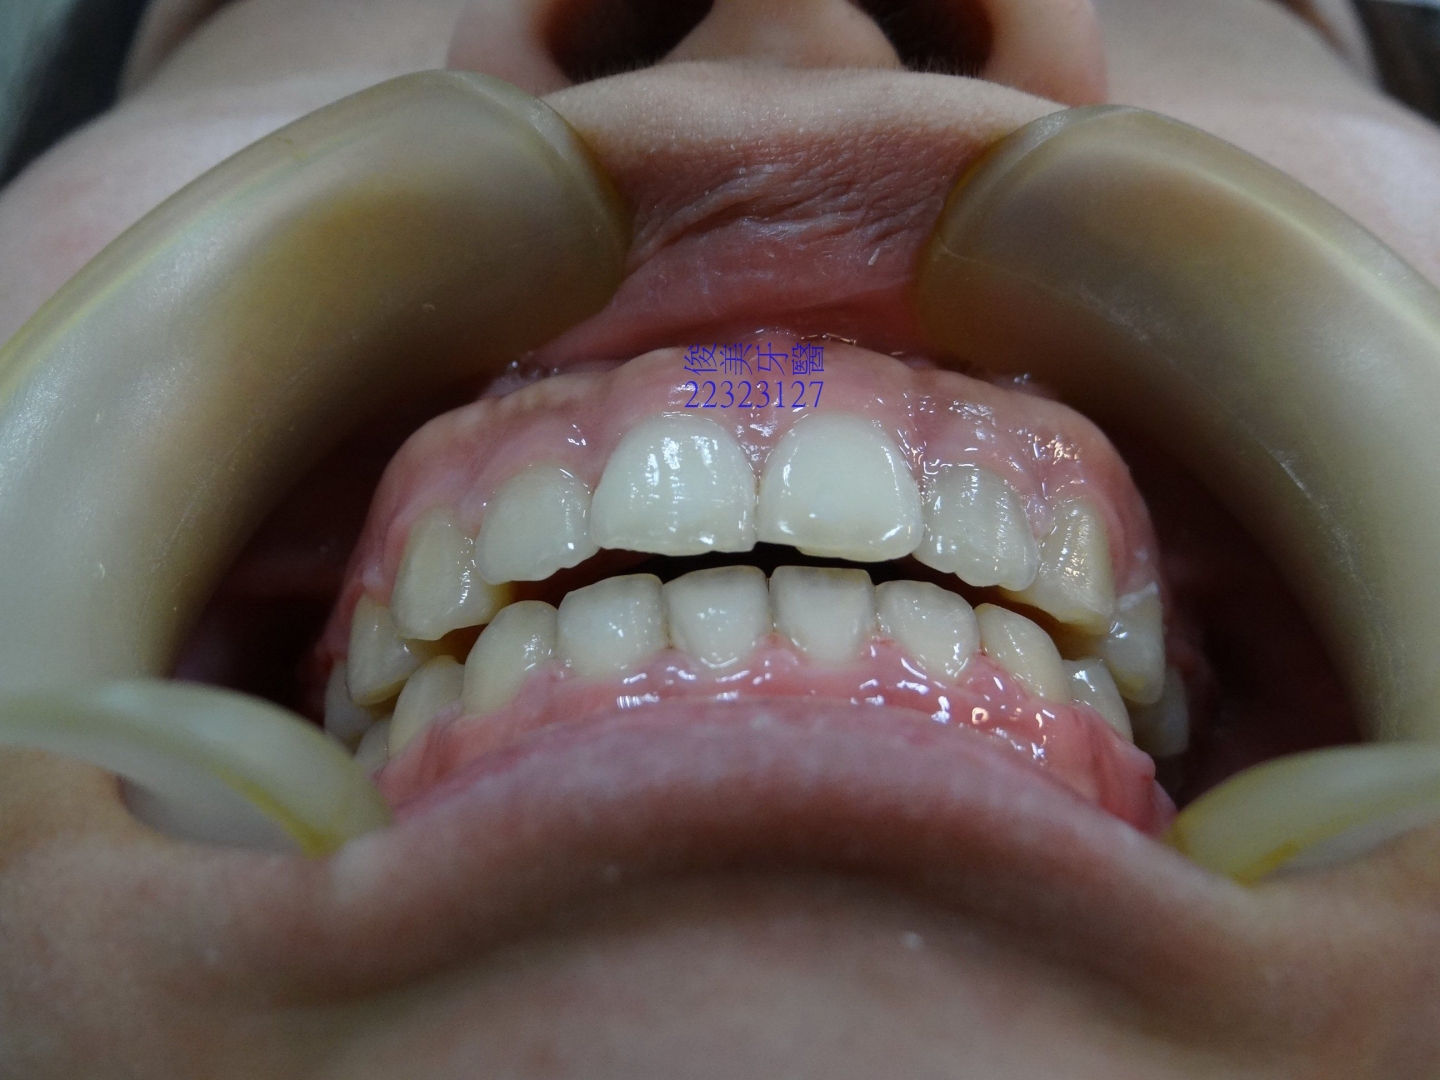

![]() 患者於門診中表示,牙齒很擁擠,想要改善;經醫師門診後,建議患者進行矯正治療即可改善。 ![]() 牙齒重疊... ![]() 有深咬現象... ![]() 上顎狀況... ![]() 下顎狀況... ![]() 左側咬合,牙齒往舌側傾斜...... . ![]() 右側咬合,牙齒往舌側傾斜...... ![]() 治療中....擁擠和深咬已改善.... ![]() 牙齒往後移.....將牙齒齒軸回正一點。 ![]() 治療結束,拆除矯正器了............. ![]() 患者好開心......牙齒整齊後,笑容更可愛了。 ![]() 也沒有暴牙的狀況。 ![]() 上顎牙弓狀況。 ![]() 下顎牙弓狀況。 ![]() 右側咬合狀況。 ![]() 左側咬合狀況。 ![]() 已拆除超過5年,依舊配戴維持器,保持最佳狀態。 |